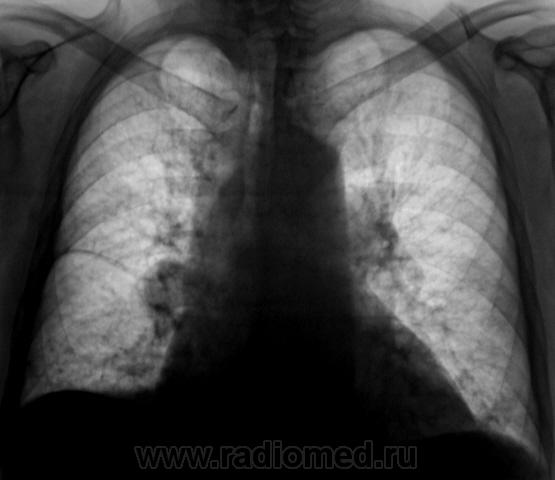

Произведены томограммы.

Здравствуйте Almo! Томограммы выполнены в стандартных срезах - 7, 9, 11 см.

На "томо" шикарно видно:

1. Гиповентиляцию правого лёгкого.